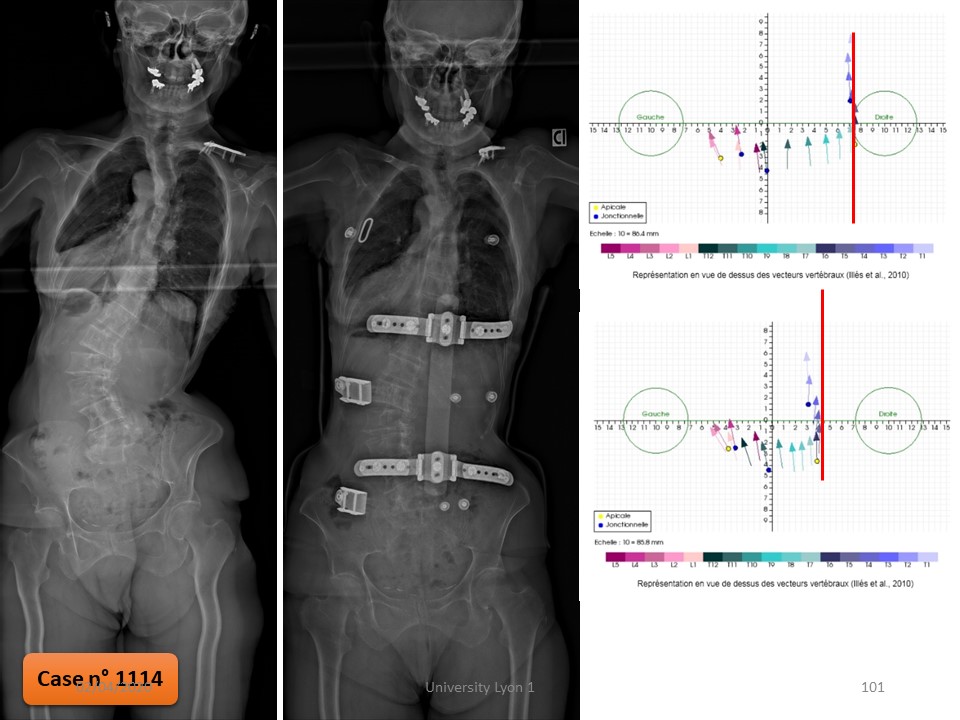

Oly scoliosis was discovered at the age of 2 years with an initial curvature of 30°. The first Milwaukee brace put in place was unsupported and a Chêneau brace by counter worn well for 3 years. Despite good compliance, the angulation progresses, and we see her at the age of 8 years with an angulation of 42°. |

|

Under the Chêneau brace, the angulation is reduced to 25°, essentially in the lower part of the scoliosis. |

The ARTbrace is much more corrective in both the frontal and sagittal planes. |

6 months after fitting, the angulation without brace is 17°. |